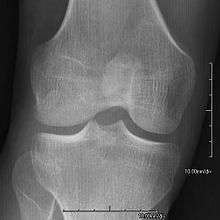

- Patellar involvement is present in approximately 90% of patients; however, patellar aplasia occurs in only 20%.

- In instances in which the patellae are smaller or luxated, the knees may be unstable.

- Exostoses arising from the posterior aspect of the iliac bones ("iliac horns") are present in as many as 80% of patients; this finding is considered pathognomonic for the syndrome.

The hallmark features of this syndrome are poorly developed fingernails, toenails, and patellae (kneecaps). Sometimes, this disease causes the affected person to have either no thumbnails or a small piece of a thumbnail on the edge of the thumb. The lack of development, or complete absence of fingernails results from the loss of function mutations in the LMX1B gene. This mutation may cause a reduction in dorsalising signals, which then results in the failure to normally develop dorsal specific structures such as nails and patellae.[8] Other common abnormalities include elbow deformities, abnormally shaped pelvic (hip) bones, and kidney (renal) disease.